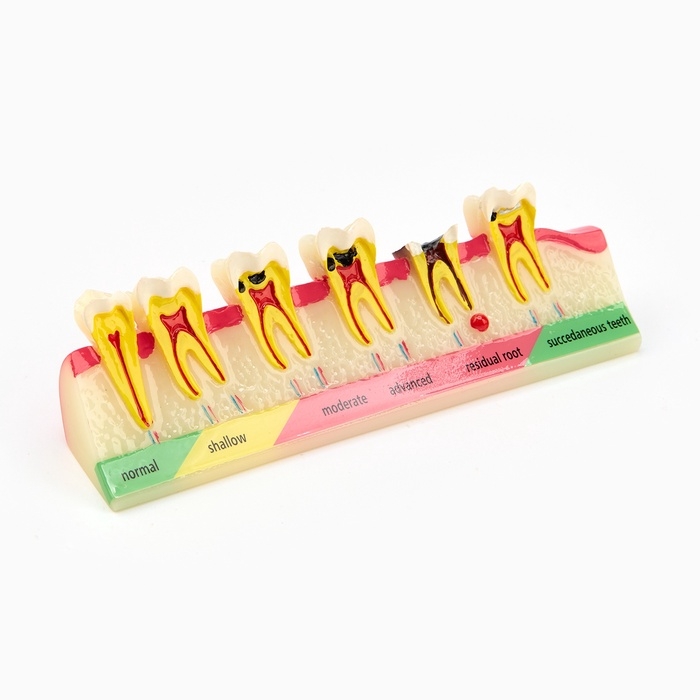

Анатомические модели

ЕКБ 41

No Brand, артикул: 7072360